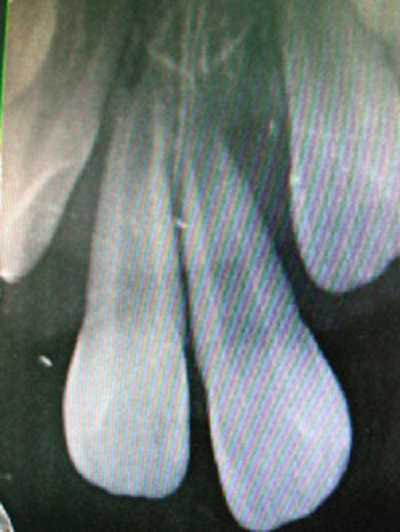

Khám lâm sàng cho thấy: gai nướu răng cửa hàm trên sưng đỏ, 2 răng cửa hàm trên bên phải lung lay độ 3, răng cửa hàm trên bên trái lung lay độ 4, cả 2 răng này tụt nướu nhiều, lộ cổ răng 1.3 mm. Chụp phim Xquang thấy tiêu xương nhiều ở vùng cổ răng, răng cửa hàm trên bên trái trồi khỏi ổ răng 1/3 chiều dài chân răng.

Nguyên nhân xảy ra hậu quả trên là do bé đã bị điều trị chỉnh răng sai phương pháp. Lý do thứ nhất là dùng thun cột 2 răng cửa với lực quá mạnh sẽ làm tiêu xương theo hướng lực kéo, phần khoảng trống còn lại không kịp tạo xương để bù đắp nên làm cho răng lung lay và đau nhức nhiều.

Lý do thứ hai là do hình dạng răng thon nhỏ về phía cổ răng nên thun cột có khuynh hướng co trượt về phía cổ răng gây đứt dây chằng nha chu, gây tiêu xương quanh cổ răng và làm răng trồi về phía mặt nhai. Nếu để muộn hơn, hai răng của bé sẽ tự văng ra khỏi xương hàm, bé sẽ vĩnh viễn mất hai răng này.